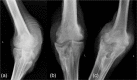

A 7-year-old female ostrich (Struthio camelus) presented with lameness, left intertarsal joint swelling and a healing wound on the caudomedial aspect of the joint. Synovial culture revealed Corynebacterium species and radiographs were consistent with progressive septic arthritis. Multiple treatments were attempted including through-and-through joint lavage, intra-articular antibiotics, caudomedial arthrotomy, and regional limb perfusion in conjunction with systemic antibiotics and analgesia. Euthanasia was ultimately performed due to prolonged recumbency and poor prognosis. This report describes novel therapies and a surgical approach utilized for treatment of intertarsal septic arthritis in an ostrich and exemplifies the poor prognosis described in other species presenting with non-responsive septic arthritis of critical joints.